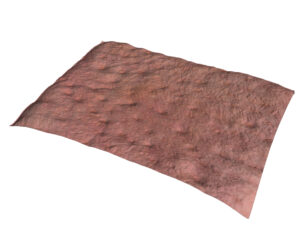

You can also perform 3D acquisitions of the skin surface. Thanks to a technique called stereo photometric, the C-Cube analyses several images under different lighting conditions. The software estimates surface normals. Combined with geometric calibration, it produces elevation information at every pixel.

Thanks to its unique ability to measure 3D parameters, it is possible to measure button elevation in terms of peak height (Sp) and total amplitude (Sz), proving that the product under test has an effect if the peak elevation decreases over time.

Pimple elevation Peak height and amplitude

The C-Cube is undeniably the best option for evaluating even the most subtle changes. Beyond measuring pimple elevation, it is able to observe very small signs of acne before they worsen with inflammation. This is equivalent to measuring the texture of the skin, invisible to the naked eye.

3D analysis provides an additional dimension of pore depth. The 3D approach improves the sensitivity of pore detection. It can then be used to assess the depth of the pores and their possible filling.